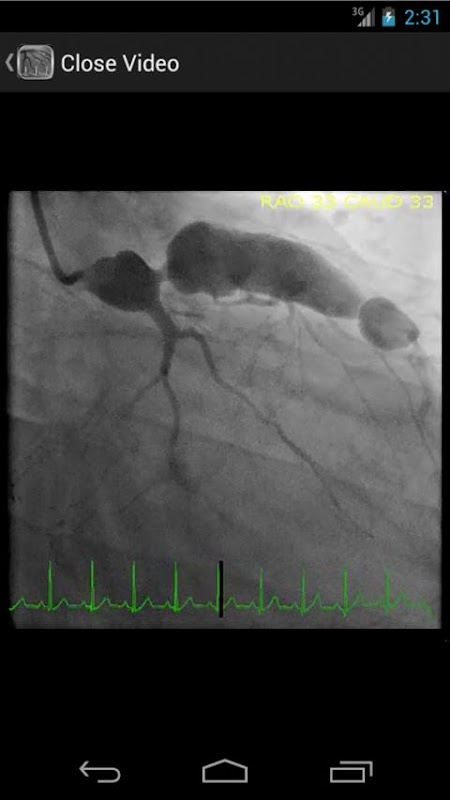

* Base de données consultable contenant plus de 30 vidéos (coronarographies, ventriculogrammes et aortograms) des deux résultats communs et rares dans le laboratoire de cathétérisme cardiaque